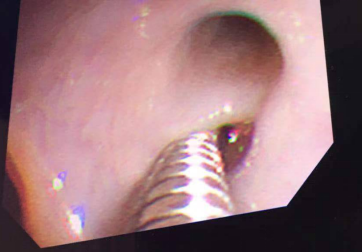

在医院分管领导和科室主任的支持下,2019年12月26日与麻醉科共同协作,儿科儿童电子支气管镜团队首次对年仅1月余的患儿在全麻下使用了2.8mm直径的电子支气管镜实施电子支气管镜检查及治疗术,手术历经2个多小时。在镜下查见患儿的声带、后联合水肿,有少许白色分泌物附着,漏斗部充血、糜烂,气管内膜充血、水肿,左、右肺充血水肿明显炎症非常重。

医生们立即在支气管镜下给予了患儿肺泡灌洗并用药物异烟肼原液0.1g肺内保留治疗,灌洗出的液体浑浊,在术后继续给予患儿吸氧和雾化治疗。